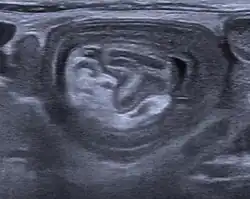

An ultrasound shows a target sign—characteristic for intussusception

An intussusception is often suspected based on history and physical exam, including observation of Dance's sign. A digital rectal examination is particularly helpful in children, as part of the intussusceptum may be felt by the finger. A definite diagnosis often requires confirmation by diagnostic imaging modalities. Ultrasound is the imaging modality of choice for diagnosis and exclusion of intussusception, due to its high accuracy and lack of radiation. The appearance of target sign (also called "doughnut sign" on a sonograph, usually around 3 cm in diameter, confirms the diagnosis. The image seen on transverse sonography or computed tomography is that of a doughnut shape, created by the hyperechoic central core of bowel and mesentery surrounded by the hypoechoic outer edematous bowel.[10] In longitudinal imaging, intussusception resembles a sandwich.[10] It is also called "pseudokidney" sign because hyperechoic tubular centre is covered by a hypoechoic rim producing a kidney-like appearance.[11]